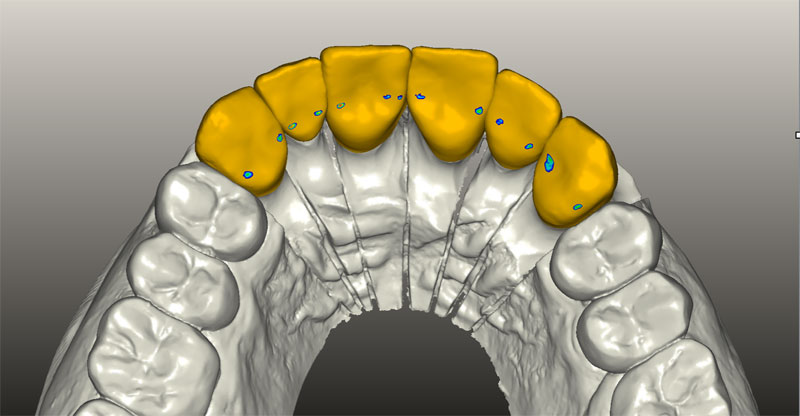

Рентгенография небного шва: Медицинские исследования и диагностика